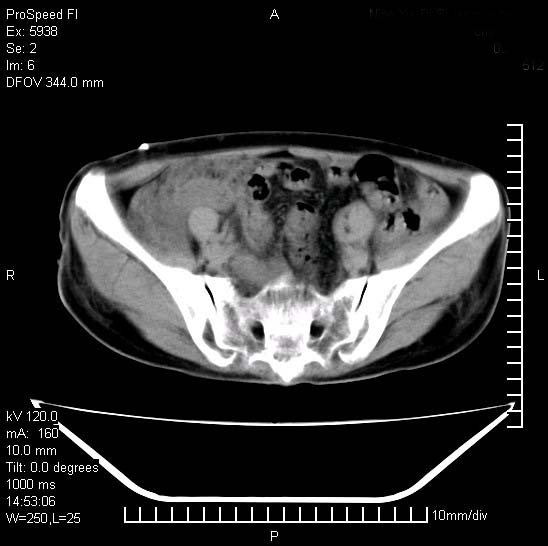

反复小腹疼痛,盆腔积液3年,无发热,曾抗痨一段时间。

右下腹肠管壁增厚,边缘有侵润改变及点状低密度影,内侧可见局限性肿块。考虑-----淋巴瘤或增生型肠结核----盆腔积液-----建议肠镜检查

考虑盆腔及右下腹感染性病变(结核可能)。

结核性腹膜炎伴积液。右侧髂骨骨窗看看,是否有骨质破坏。

提示结核性腹膜炎合并盆腔积液。建议查ppd或tb抗体。